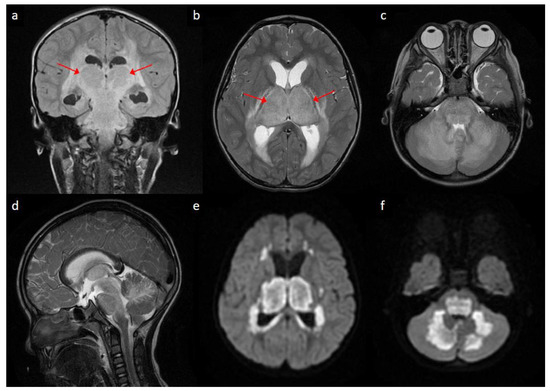

Acute Necrotizing Encephalopathy in a Four-Year-Old Boy